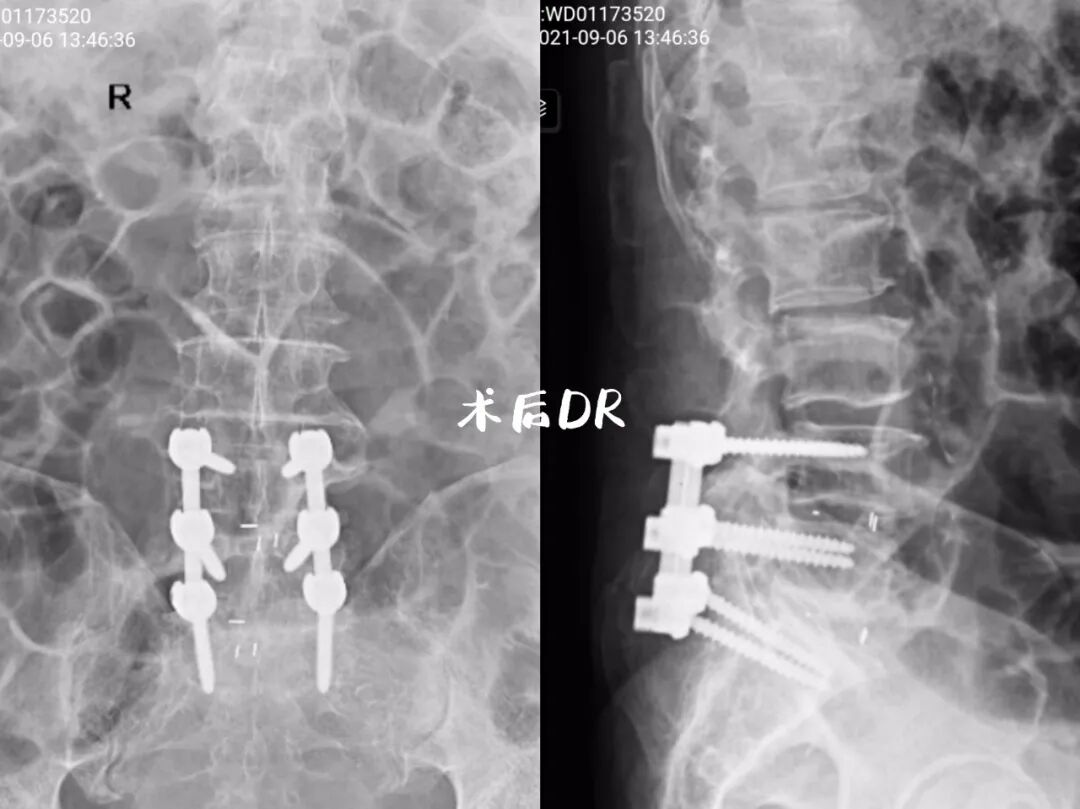

专家团队为朱先生制定了详细的治疗方案,有计划、分步骤的为其进行了长达5个小时的腰椎后路椎管减压,腰椎滑脱复位矫正融合内固定手术。术后可以直立行走,双下肢麻木疼痛症状明显改善。